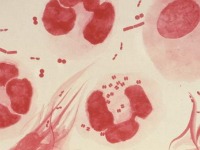

Científicos hallaron en Japón una cepa de una ¨superbacteria¨ de la gonorrea que es resistente a todos los antibióticos recomendados y que podría transformar la infección que suele ser fácilmente tratable en una amenaza para la salud pública mundial.

La nueva cepa de la enfermedad de transmisión sexual -denominada H041- no puede eliminarse con ningún tratamiento actualmente aconsejado para combatir la gonorrea, lo que lleva a los médicos a tener que probar medicinas no evaluadas hasta el momento contra la condición.

Magnus Unemo, del Laboratorio Sueco de Referencia para la Neisseria Patogénica, halló la cepa con colegas de Japón en muestras provenientes de Kioto y la describió como ¨alarmante¨ y ¨predecible¨.

El análisis de la cepa que realizó el equipo reveló que es extremadamente resistente a todos los antibióticos de la clase cefalosporina, los últimos medicamentos efectivos que quedan para tratar la gonorrea.